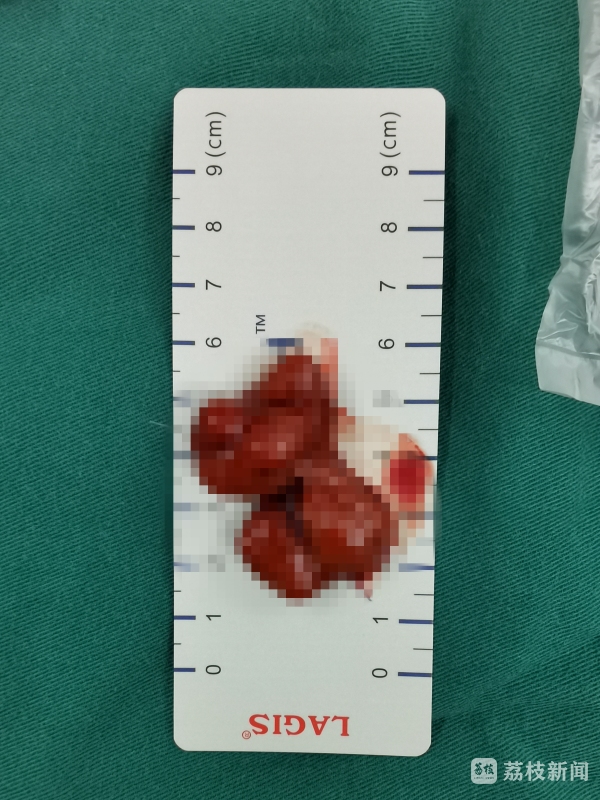

3月9日,该院普外科黄磊主任医师为姗姗进行了腹腔镜下的息肉切除。“曾经,这样的手术都需要切开腹部,创伤很大;后来常规腹腔镜手术是在腹部打三个‘洞’,一个放腹腔镜,两个放手术器械。此次,我们采用了三通道单孔腹腔镜(Triport),只在肚脐上开一个2厘米左右的洞即可,术后几乎看不到明显的伤口。”黄磊说到,“在腹腔镜下,我们看到息肉很大,堵住了整个肠腔,而且呈不规则分叶状‘埋’在肠壁中,没有明显的根部。”术中,黄磊在腹腔镜下将息肉一点点剥离肠道,避免伤及肠壁。最终,手术切除的息肉直径约4厘米,足足有一个“鸽子蛋”大小。